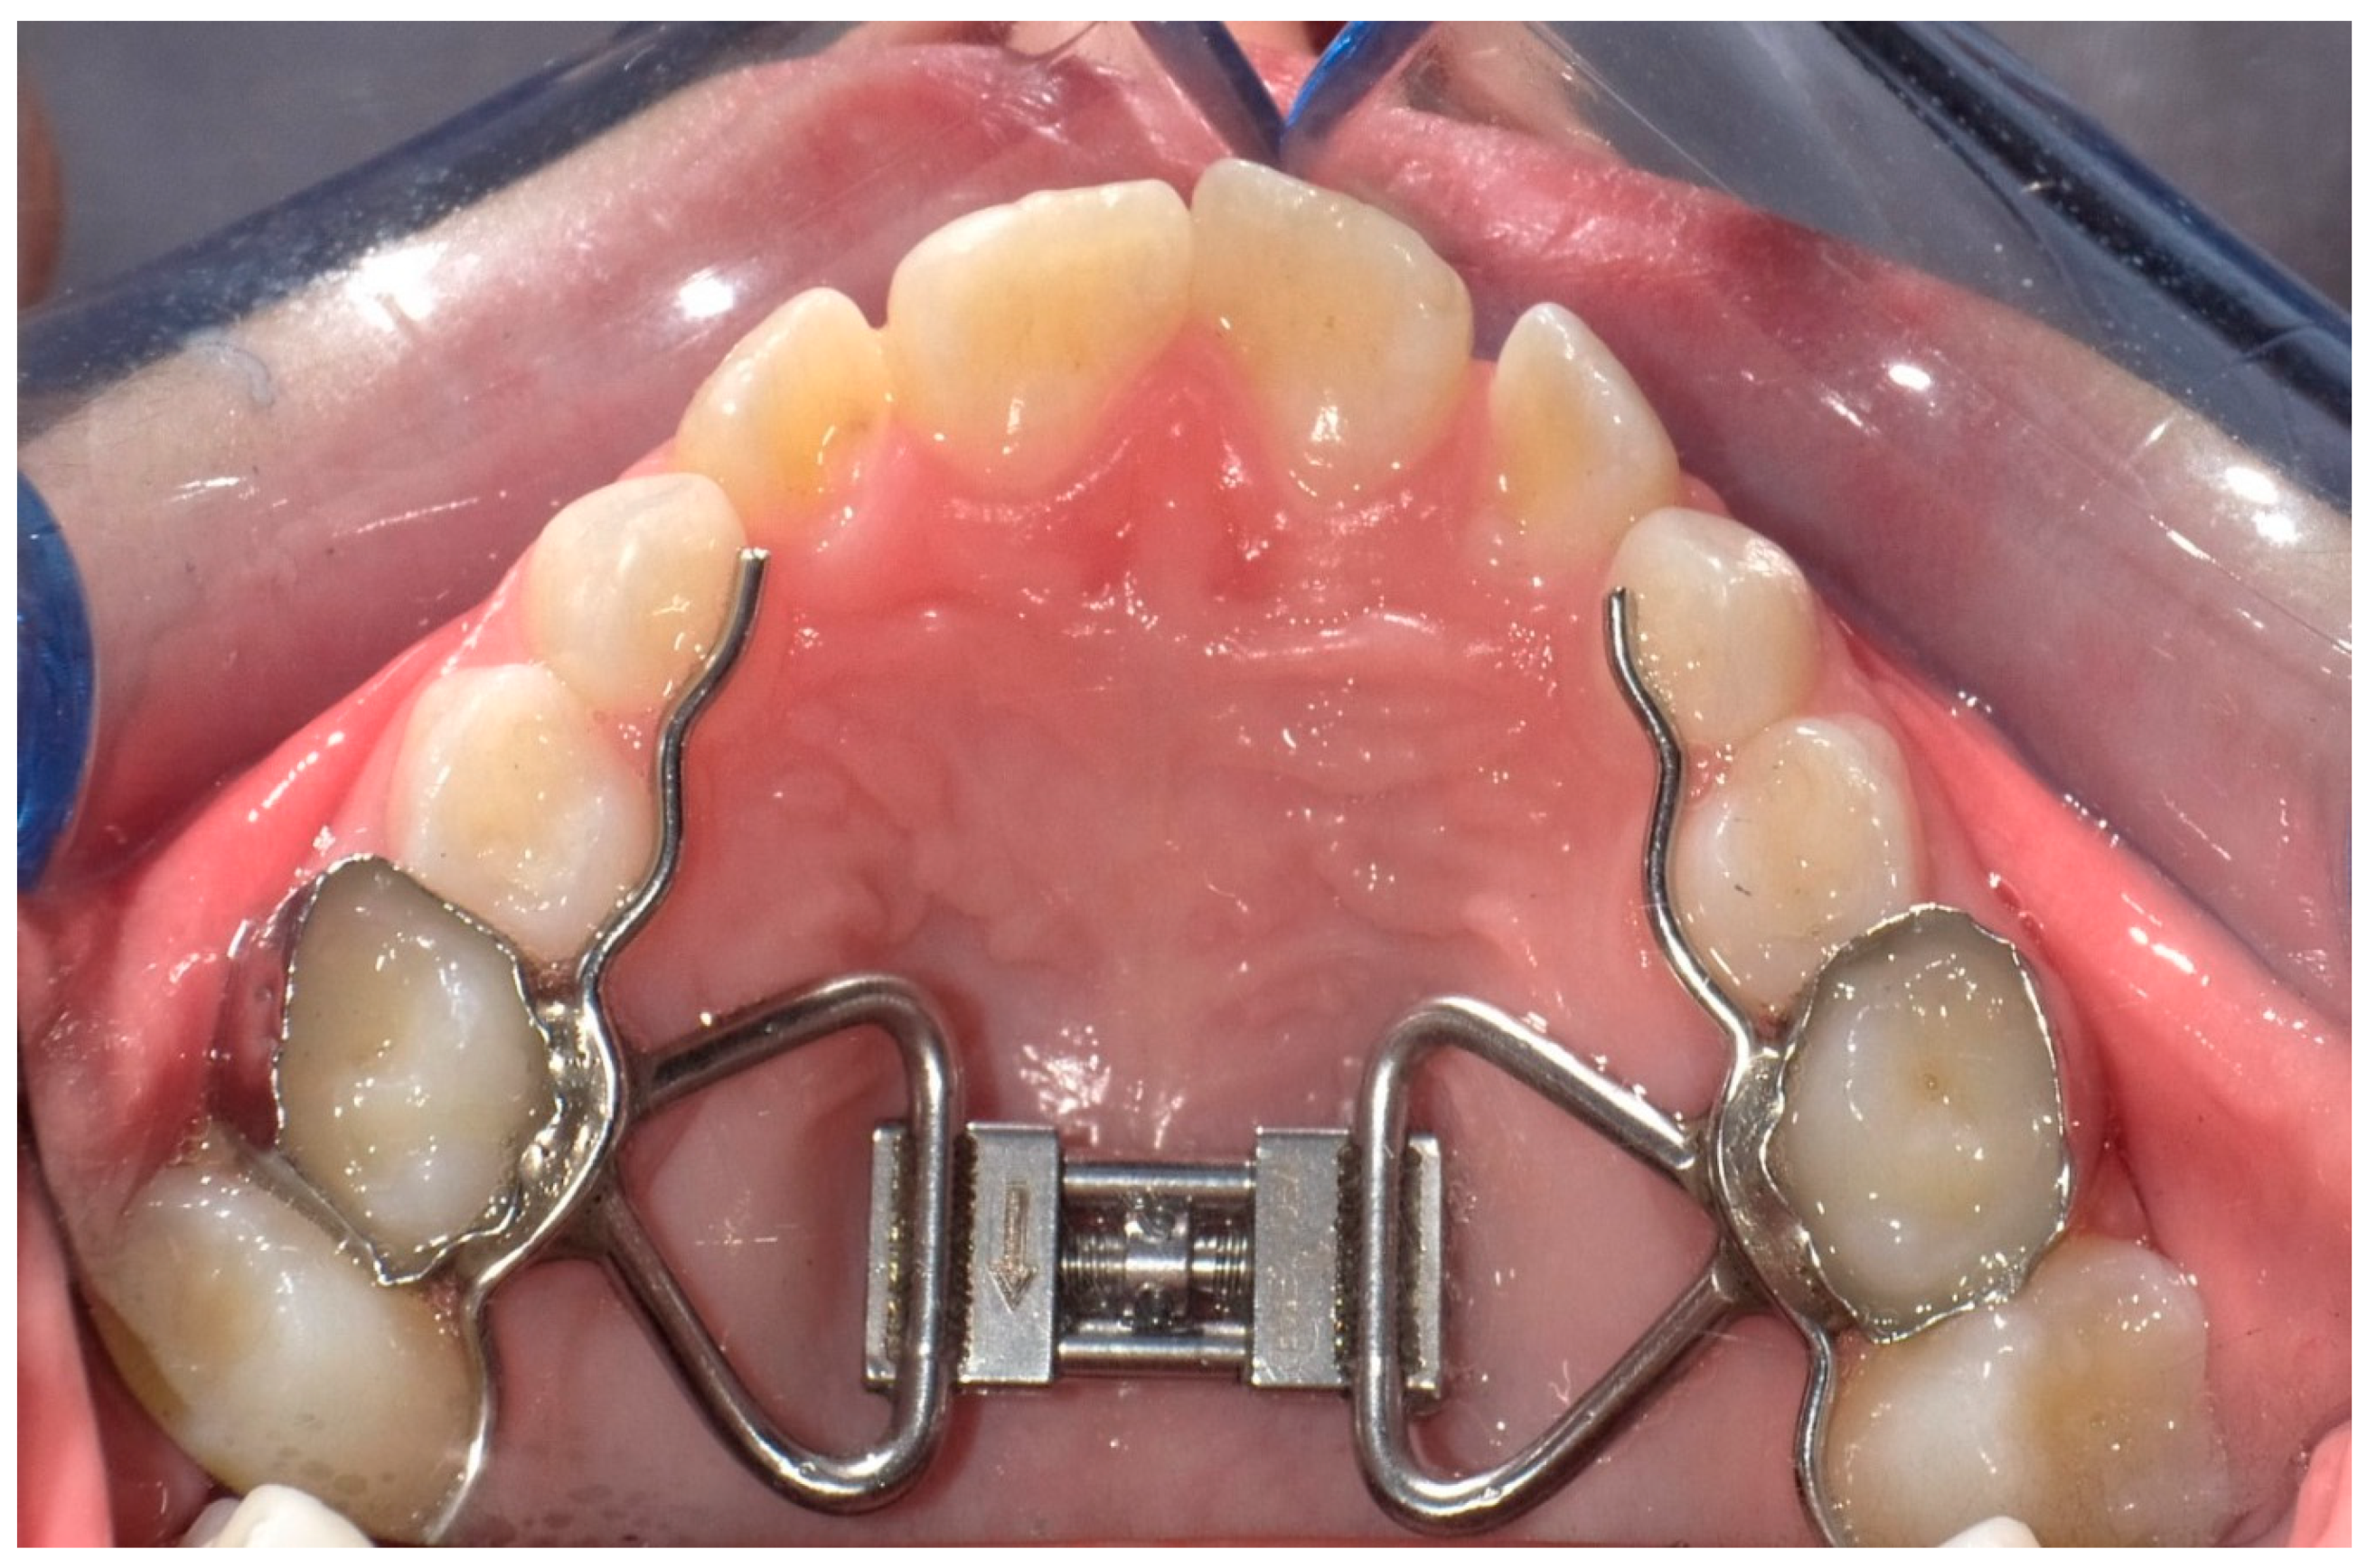

2. Materials and Methods

2.1. Study Design, Type of Participants and Inclusion Criteria